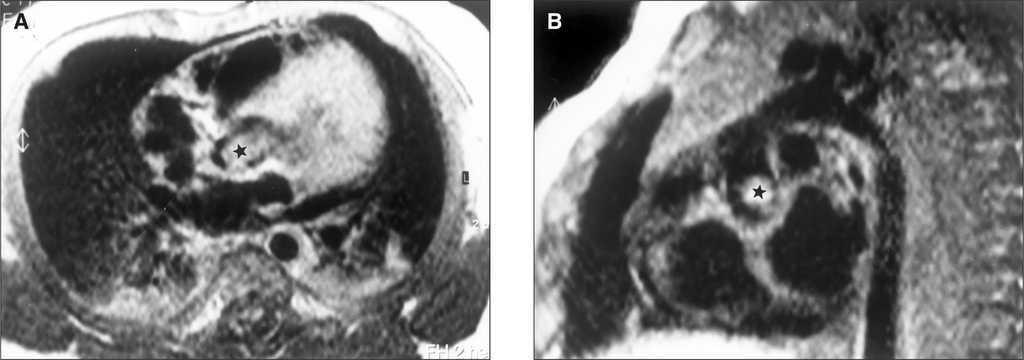

Entre los antecedentes familiares, el padre y abuelo presentaban adenomas sebáceos en cara y manchas acrómicas en tórax, y la hermana del padre, litiasis renal asociada a insuficiencia renal, en tratamiento con diálisis. Exploración: recién nacido de parto a término con un peso de 2.065 g y manchas hipocrómicas en muslos. Auscultación cardíaca: soplo sistólico eyectivo en segundo espacio intercostal derecho con irradiación a cuello. Electrocardiograma y radiografía de tórax dentro de los límites de la normalidad. Ecocardiograma bidimensional: proyección 4 cámaras más aorta y eje largo, imagen ecogénica en la zona subaórtica de 1 cm de diámetro que en sístole protruye en la válvula aórtica obstruyéndola. La ecografía Doppler mostraba gradiente sistólico en el tracto de salida del ventrículo izquierdo de 80 mmHg. Resonancia cardíaca; en proyección frontal y oblicua se confirma la imagen densa de 8 mm de diámetro transverso y 11 mm de largo insertada en la zona subvalvular (fig. 1A), pasa a la raíz aórtica en sístole (fig. 1B). La resonancia magnética (RM) cerebral realizada posteriormente fue normal.

Figura 1. A) Resonancia. El tumor en cavidad ventricular en la zona subaórtica.B) Resonancia. El tumor pasa a la raíz de la aorta creando una obstrucción grave.